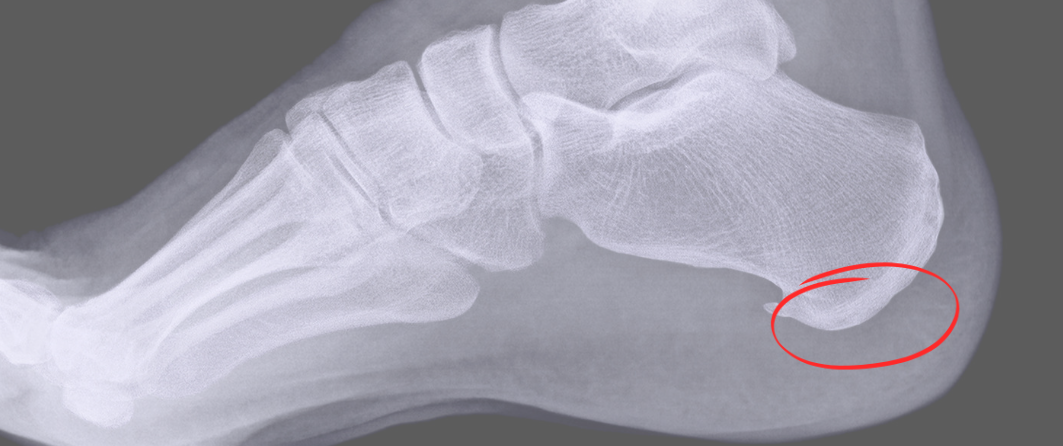

Wo genau die Ursachen für Fersensporn liegen, ist noch nicht abschließend geklärt. Ein möglicher Grund ist, dass der Körper tatsächlich einen Heilungsversuch unternommen hat. Sind die Sehnen im Fuß überlastet und kommt es in Folge der Überlastung zu leichten Rissen oder zu Entzündungen der Sehnen, lagert der Körper Kalk dort ein. Aus diesem Kalk entwickeln sich schließlich kleine Objekte, die nicht einmal stören müssen: Nur ein kleiner Teil der Betroffenen hat durch einen Fersensporn tatsächlich Schmerzen. Sichtbar sind die Ablagerungen im Fuß beim Röntgen. In aller Regel werden beide Füße geröntgt, da meist beide Fersen betroffen sind. Da diese Schmerzen, wenn sie schließlich dauerhaft auftreten, für große Unannehmlichkeiten sorgen, ist das Verschwinden des Fersensporns wünschenswert. Heilungsmethoden gibt es aktuell mehrere. Eine Operation zählt zwar zu diesen Methoden, doch ist sie meistens gar nicht erforderlich und die Heilung ist auch nicht unbedingt garantiert.